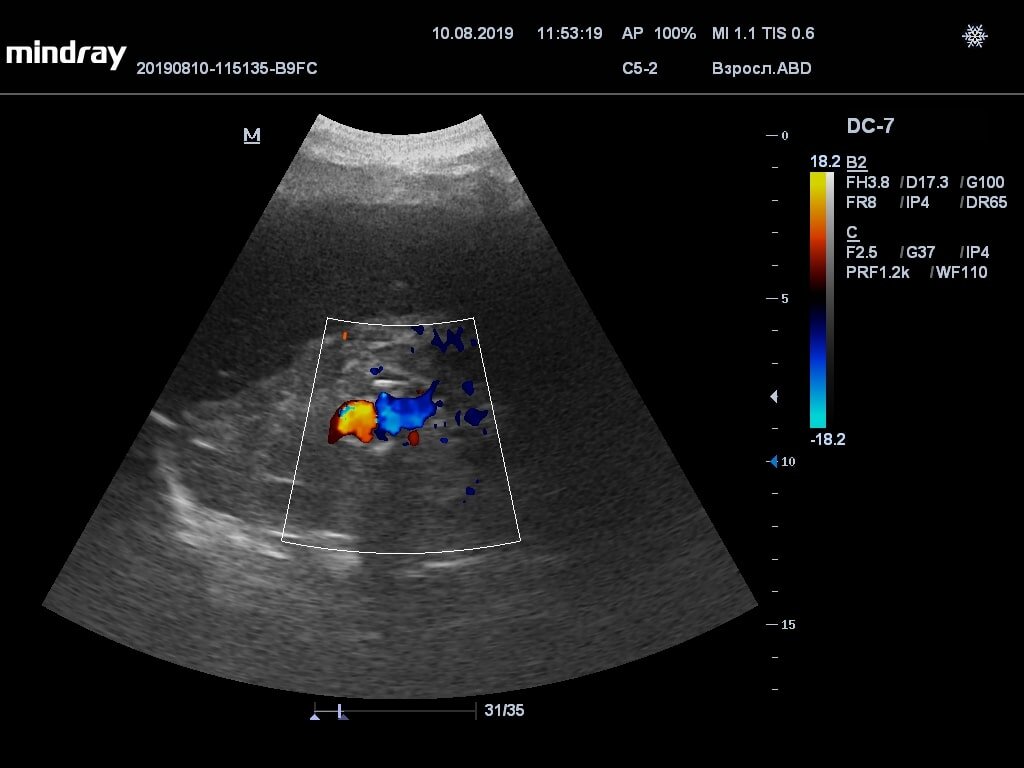

• УЗИ артерий, ультразвуковое исследование с эффектом Доплера.

Патология может никак себя не проявлять, выпячивание стенок артерии обычно обнаруживают при проведении ультразвукового исследования почек или системы кровообращения. Аневризма правой или левой почечной артерии может вызывать различные симптомы: